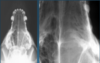

What is shown in these images?

Top: -normal Bottom: -secondary renal hyperparathyroidism -illusion of teeth "floating" in soft tissue